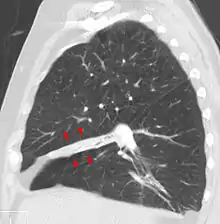

Rounded atelectasis

In rounded atelectasis (folded lung or Blesovsky syndrome[15]), an outer portion of the lung slowly collapses as a result of scarring and shrinkage of the membrane layers covering the lungs (pleura), which would show as visceral pleural thickening and entrapment of lung tissue. This produces a rounded appearance on x-ray that doctors may mistake for a tumor. Rounded atelectasis is usually a complication of asbestos-induced disease of the pleura, but it may also result from other types of chronic scarring and thickening of the pleura.